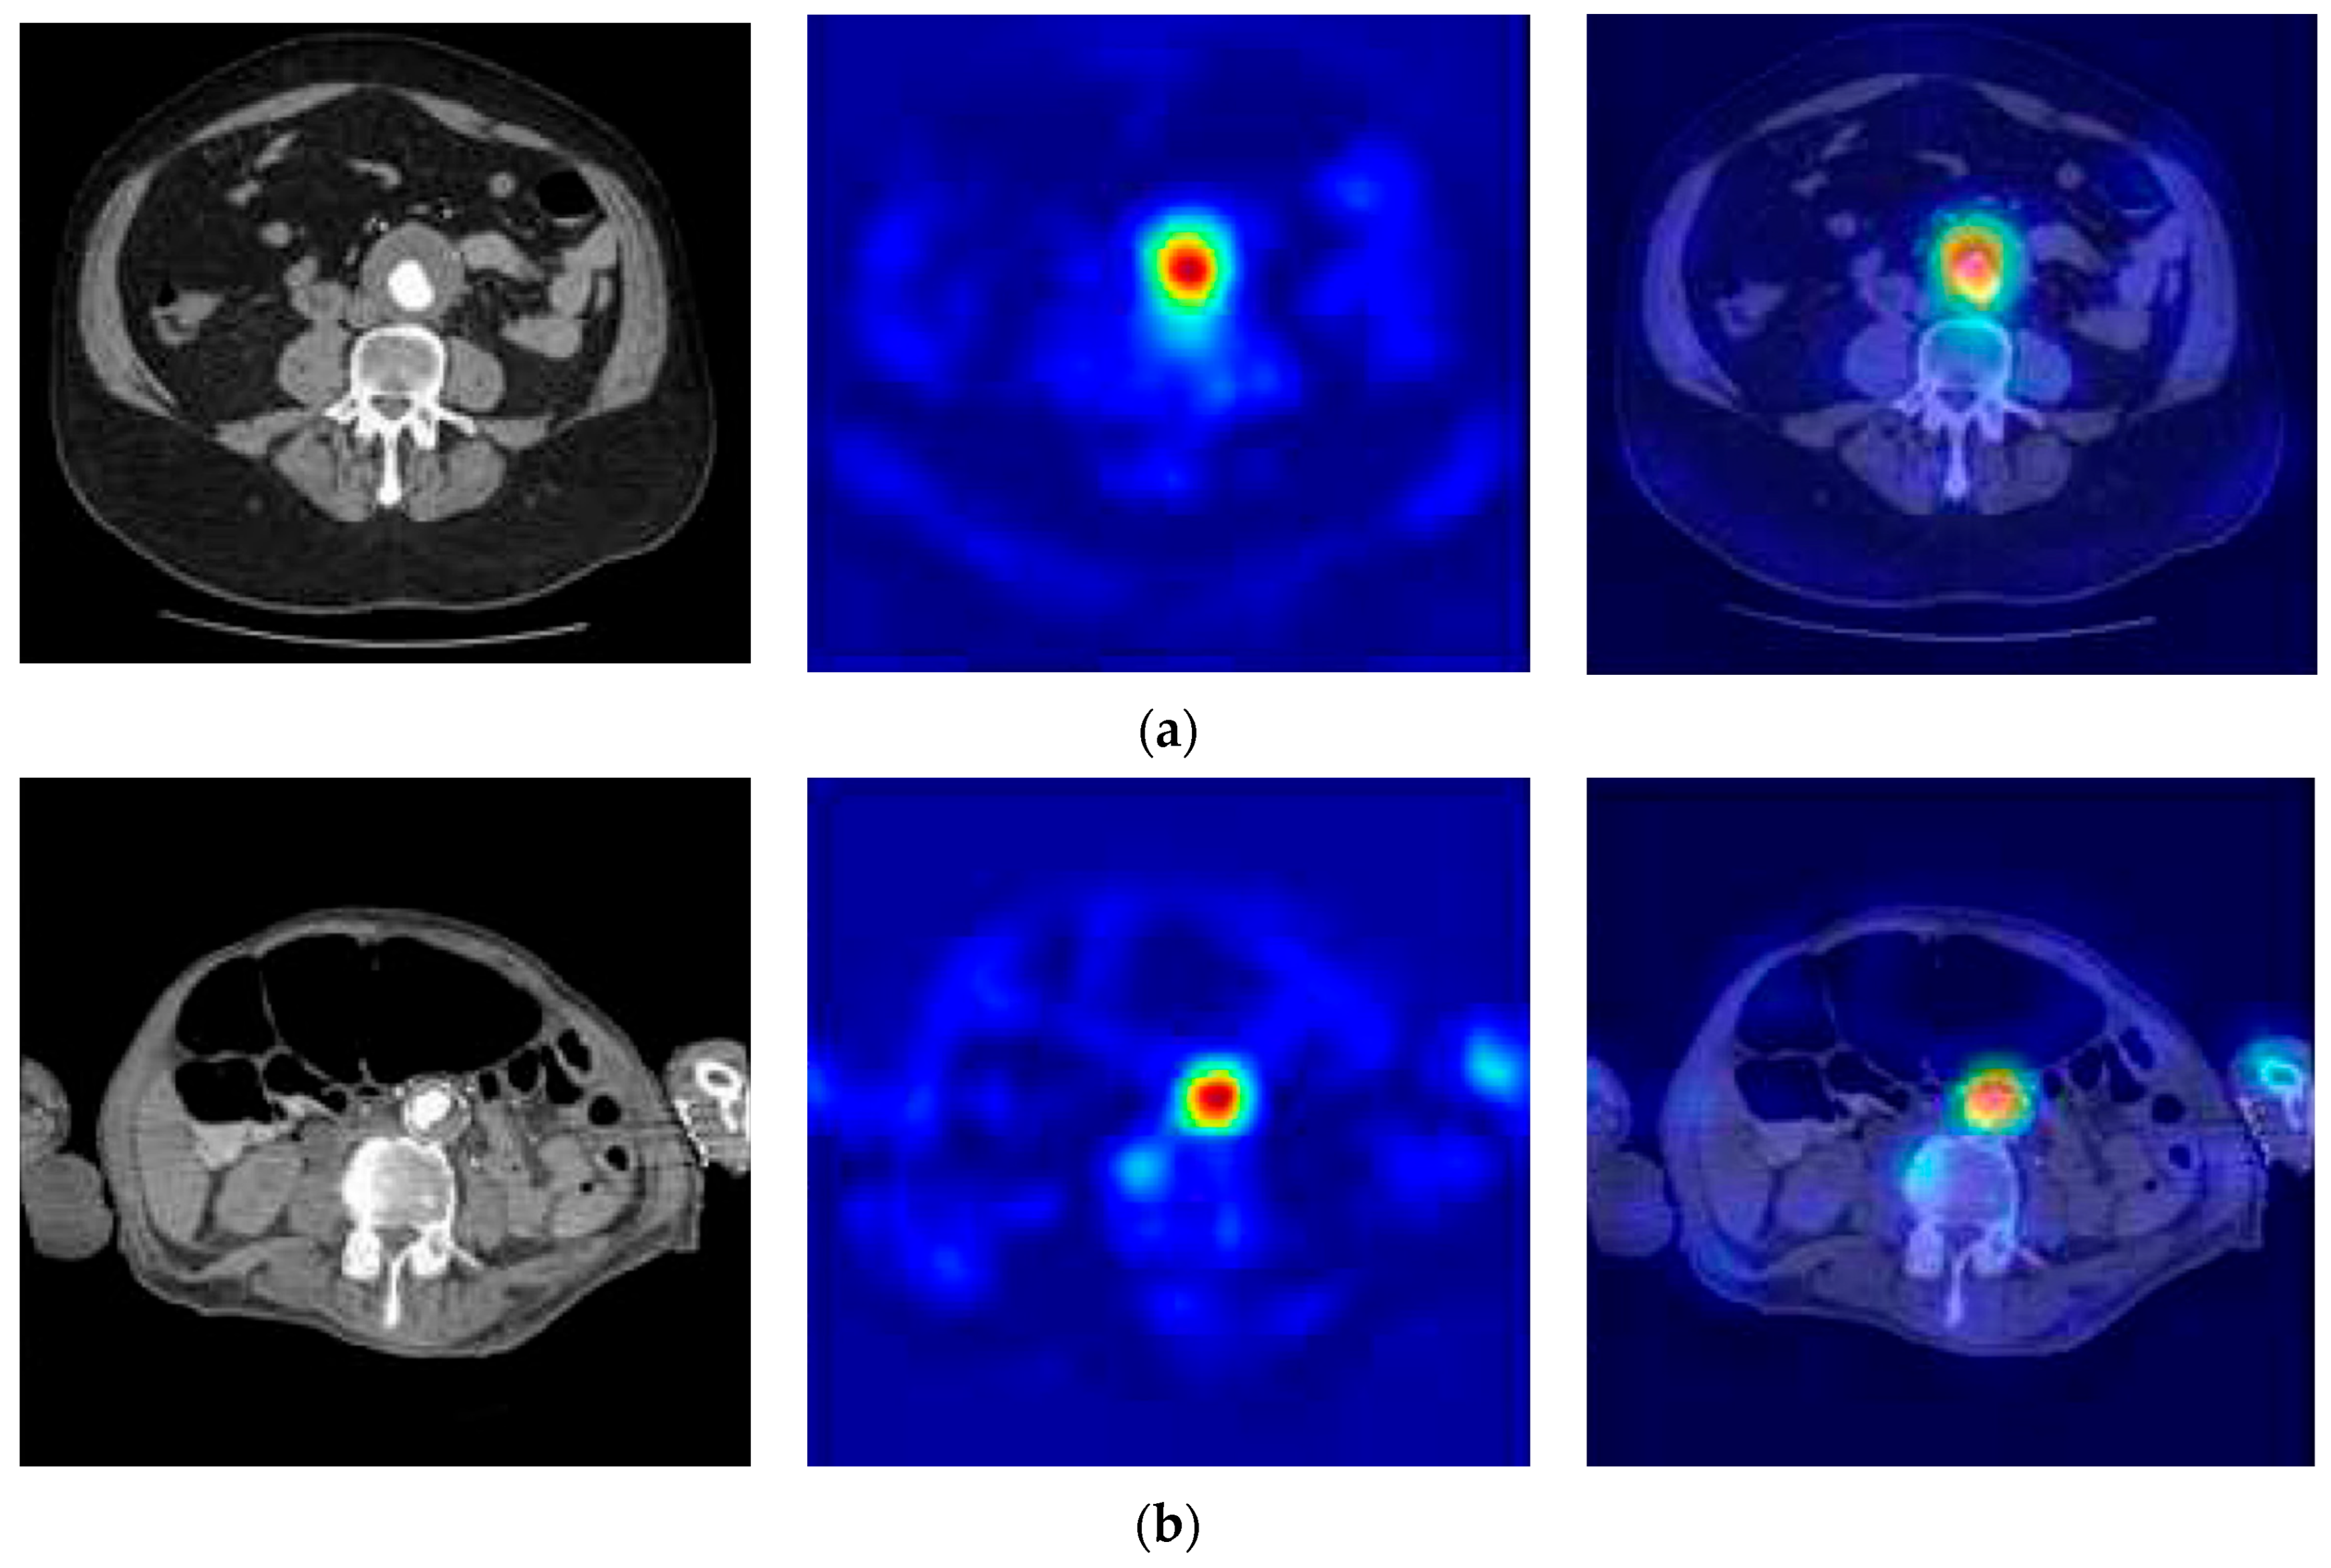

3.3. The Performance Results of the AAA and AAD Diagnosis and Classification